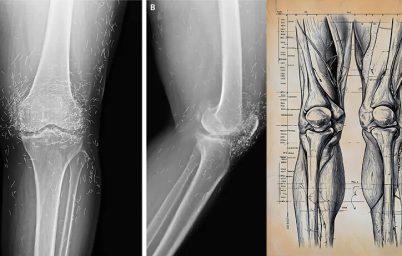

200'den fazla çalışmanın kapsamlı bir incelemesi, yürüyüş ve bisiklet gibi aerobik egzersizlerin diz osteoartriti için en iyi ağrı giderici ve hareketlilik artışı sağladığını ortaya koydu. Diğer...